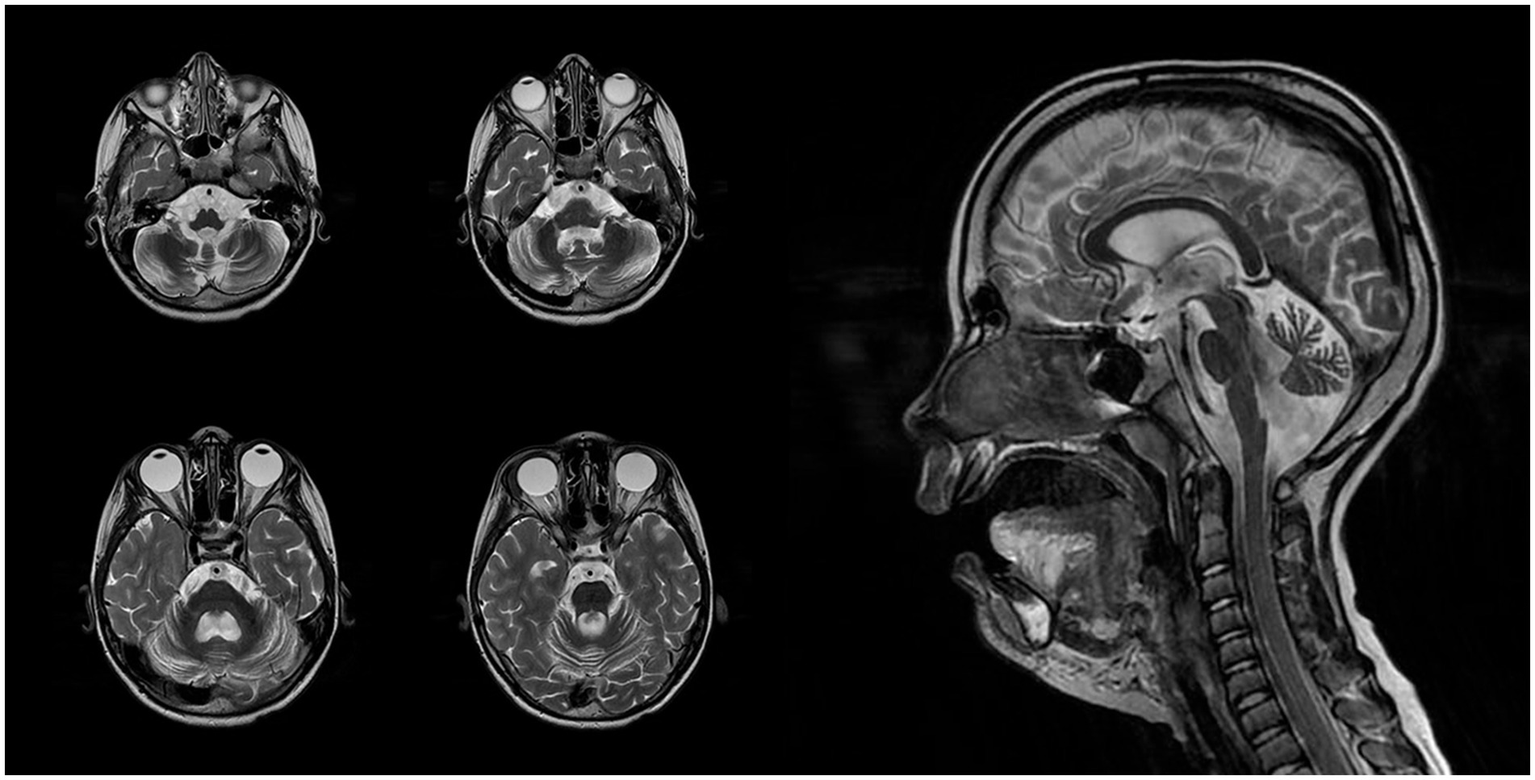

At the age of 5, the patient underwent a brain MRI to evaluate the feasibility and scope of potential surgical intervention. Imaging revealed cerebellar volume loss (Figure 1A) and periventricular leukoencephalopathy in the frontal and parietal white matter (Figure 1B). These findings indicated that the observed developmental regression and seizures were unlikely to be related to functional neurological disturbances or perinatal hypoxic–ischemic injury, but instead pointed toward a lysosomal storage disorder. Hamburg Scale for LINCL was 11 at that time. A neck mass was surgically excised, with histological confirmation of lymphatic malformation.

Figure 1

(A) Axial T2-weighted slice demonstrates excessive widening of cerebellar sulci and expansion of cisternal spaces in the posterior cranial fossa, reflecting moderate cerebellar atrophic volume loss. (B) Axial T2 FLAIR slice reveals mild periventricular leukoencephalopathy in the white matter of the frontal and parietal lobes. (C) Sagittal T1-weighted slice shows reduced cerebellar volume with an enlarged posterior cranial fossa, clearly illustrating cerebellar atrophy.

The first MRI was performed at the age of 5 years (Figure 1). An axial T2-weighted image demonstrated pronounced widening of the cerebellar sulci and enlargement of the cisternal spaces in the posterior cranial fossa, indicative of moderate cerebellar volume loss consistent with cerebellar atrophy (Figure 1A). An axial T2-FLAIR image revealed mild periventricular leukoencephalopathy involving the white matter of the frontal and parietal lobes (Figure 1B). A sagittal T1-weighted image showed reduced cerebellar volume and expansion of the posterior cranial fossa, clearly illustrating cerebellar atrophy (Figure 1C). A follow-up MRI was conducted at the age of 7 years and 6 months due to progression of neurological symptoms (Figure 2). From a dynamic perspective over the observed interval, no significant changes were noted compared to the previous imaging. An EEG performed at 7 years and 6 months during wakefulness (Figure 3A) revealed cortical rhythms inconsistent with the patient’s age, characterized by generalized disorganization and epileptiform discharges. Daytime EEG recordings during both wakefulness and sleep (Figure 3B) confirmed markedly disorganized cortical activity with prominent epileptiform features. WES identified a homozygous variant: chr13:76995929AG > A, CLN5(NM_006493.4):c.368del (p.Arg123LysfsTer4), which was classified as pathogenic according to ACMG criteria (PVS1, PM2, PM3). Sanger sequencing confirmed the variant and the patient’s homozygous status.